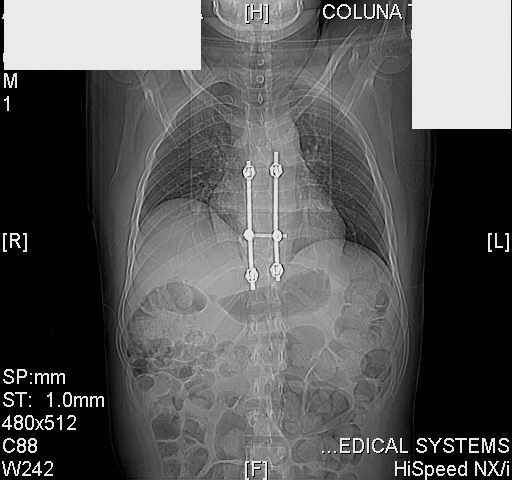

dear all (George?) Got a note this morning requesting an opinion about a patient 25 yrs froma remote area of the country who received this "excellent" stabilization of a fracturedthoracic spine over a year ago.The original neurosurgeon liberated the patient for fullactivities and rehab etc.The rehab doc wants to know what to do. Looks to me like the patientwas screwed pretty good! any offers?

Interesting case. Findings on CT: all four pedicle screws have been placed improperly inthat they miss the vertebral bodies. In addition, the screws on the left side are impingingon the decending thoracic aorta. What I do NOT know is the nature of the original injury, orwhether or not that injury has resolved. I would recommend removal of the hardware. I don'tthink it's a good idea to leave those screws where they are. If the original fracture ishealed, nothing else needs to be done.

dear Mark, all the details are not yet available but the patient is coming to see us foradvice. We probably will see him in the early new year. i thought that the 4th picture showedthe screw to enter the aorta? He is a victim of a motor vehicle crash and thoracic vertebralfracture which appears healed. He was posteriorly decompressed and this device inserted. asyou say there isno evidenece that any of the fixation enters the bodies via the pediclesistead they have passed thru and their end are no where near where they ought to be. If I amcorrect (I would prefer not to be) the aortic intima has been breached by the screw. When thetime comes to take the screw out I thought we should have control of the aorta.What do you think?